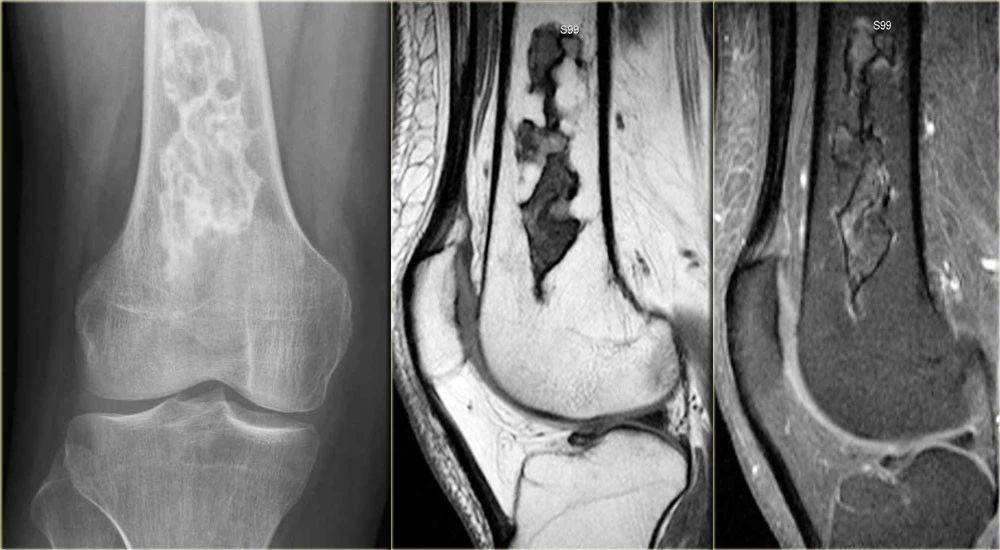

骨肉瘤常见的原发性恶性骨肿瘤。膝盖周围50%。表现:疼痛,肿块,病理性骨折。硬化症出现于肿瘤新骨形成或反应性硬化。年龄:最常见于10-25岁,但可能发生在老年患者。平片典型的表现为过渡区的虫蚀或渗出型病变,皮质破坏不规则,软组织外伸伴骨膜反应中断。骨膜反应科德曼三角:表现为肿瘤使骨膜从下面的骨头上隆起,皮质软组织延伸,破坏刚形成的骨膜新生骨,可产生放射状骨针。下图是右侧股骨骨肉瘤的图像。它在骨头内几乎看不见,但是可以看到一个累进的骨膜炎(箭头)。

0a92e618a343ad20d72a53d3014d41e1.jpg

MR矢状位T1WI和Gd增强的图像显示肿瘤体积大,浸润股骨远端大部分,并延伸至软组织。

a03e743072236df61516a8ab132b8465.jpg